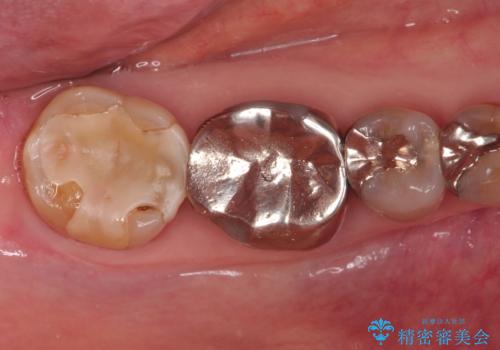

- 他院で入れたセラミックインレーがかけたことを主訴に来院されました。

他の部位にもむし歯を認めたため、優先度の高い歯から治療を行っております。

咬合力が強くかかる部分には欠けるリスクのほとんどない金属を用いることが最良ですが審美性に劣ります。

今回は白い材料での修復を希望されたため、欠けるリスクが高いセラミックインレーは避け、セラミッククラウンにて治療を行いました。